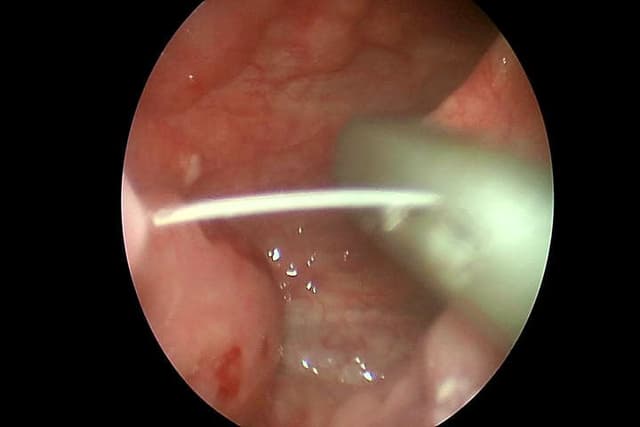

Nội soi tiêu hóa công nghệ NBI hiện đại không đau

Không còn lo lắng gặp phải các cảm giác khó chịu, buồn nôn… hiện nay, việc nội soi tiêu hóa đã trở nên dễ chịu và đơn giản hơn rất nhiều. Ngoài ra, nhờ các phương pháp tiên tiến, các bệnh lý đường tiêu hóa cũng được phát hiện dễ dàng, chính xác ngay từ […]

4 điểm khác biệt của công nghệ nội soi tiêu hóa NBI 5P

Với khả năng phát ánh sáng dải tần hẹp quan sát sắc nét lớp niêm mạc, phóng đại hình ảnh hơn 100 lần, và cực kì êm ái không khó chịu, công nghệ nội soi NBI 5P tại Hệ thống y tế Thu Cúc là lựa chọn lý tưởng giúp kiểm tra toàn diện sức […]

Công nghệ nội soi NBI 5P thế hệ mới ở Hệ thống y tế Thu Cúc giúp phát hiện sớm nhiều bệnh lý tiêu hóa, bao gồm ung thư. Trong tháng 11/2019 khách hàng nội soi còn nhận thêm 1 gói khám sức khỏe tổng quát miễn phí. Phát hiện sớm, ngăn ung thư ngay […]

Nội soi tiêu hóa công nghệ NBI 5P tại Bệnh viện Thu Cúc

[Theo báo điện tử 24H] Không chỉ trải nghiệm dịch vụ nội soi tiêu hóa không đau, không khó chịu, khách hàng khi đăng ký nội soi dạ dày đại tràng theo công nghệ NBI 5P phát hiện sớm ung thư tại Hệ thống y tế Thu Cúc sẽ được tặng thêm một gói khám […]